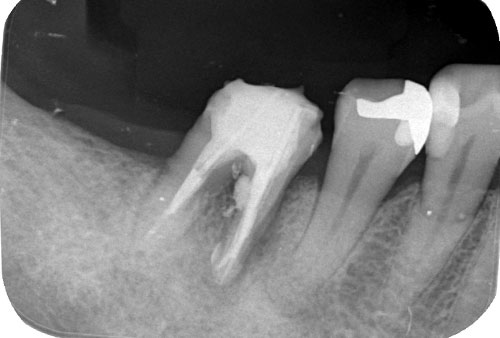

根管治療を行う前に、画像診断で形状を確認します。多くの歯科医院では「2次元」のレントゲンで撮影しますが、レントゲンでは初期の患部を見つけにくい上、根管の複雑な形状をしっかり確認するには力不足です。

そこで、当院では「3次元」で撮影ができる「CT」を利用します。CTはお口の周囲を360度回転しながら撮影するので、レントゲンでは写し出せない患部の様子が詳細にわかります。

充てん剤が根の先までしっかり入っているか、レントゲンで確認します。隙間ができている場合は、再度薬剤を入れ直し隙間を埋めていきます。

レントゲン撮影で歯の根の先までしっかりと薬剤が入っていることが確認できたら、土台を形成し、被せ物をします。